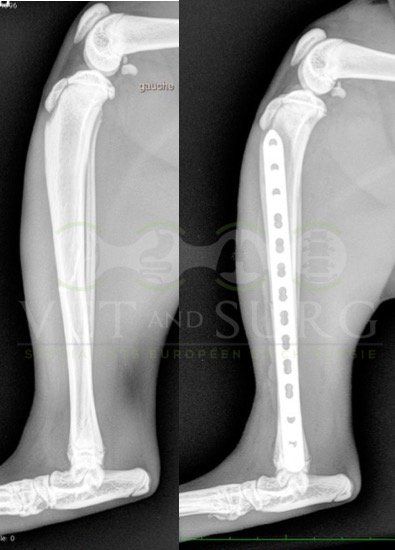

Fracture Salter-Harris sur un chaton Européen de 10 mois

Spike, chaton européen mâle de 10 mois, a été présenté en consultation pour boiterie du membre postérieur droit à la suite d'une chute depuis le 1er étage.

A la radiographie, une fracture de type Salter-harris 1 est diagnostiquée, avec déplacement de l'about discal.

Une réduction de la fracture par pose de 2 broches en croix a été réalisée.